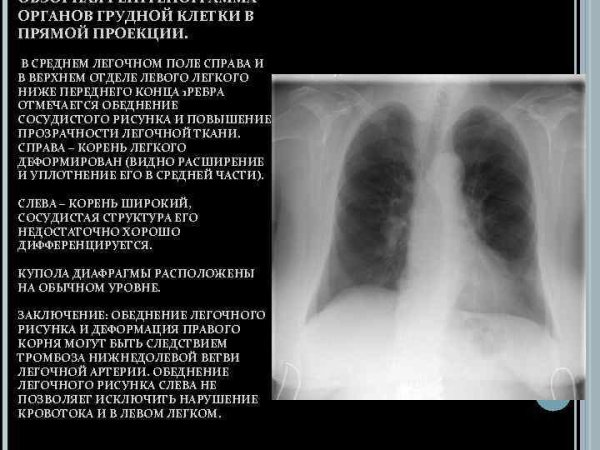

Ангиопульмонография при Тэла заключение